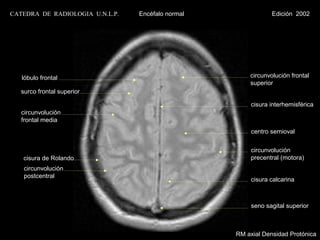

CATEDRA DE RADIOLOGIA U.N.L.P.   Encéfalo normal             Edición 2002

lóbulo frontal                                    circunvolución frontal

superior

surco frontal superior

cisura interhemisférica

circunvolución

frontal media

centro semioval

cisura de Rolando                                 precentral (motora)

postcentral

cisura calcarina

seno sagital superior

RM axial T1 con contraste